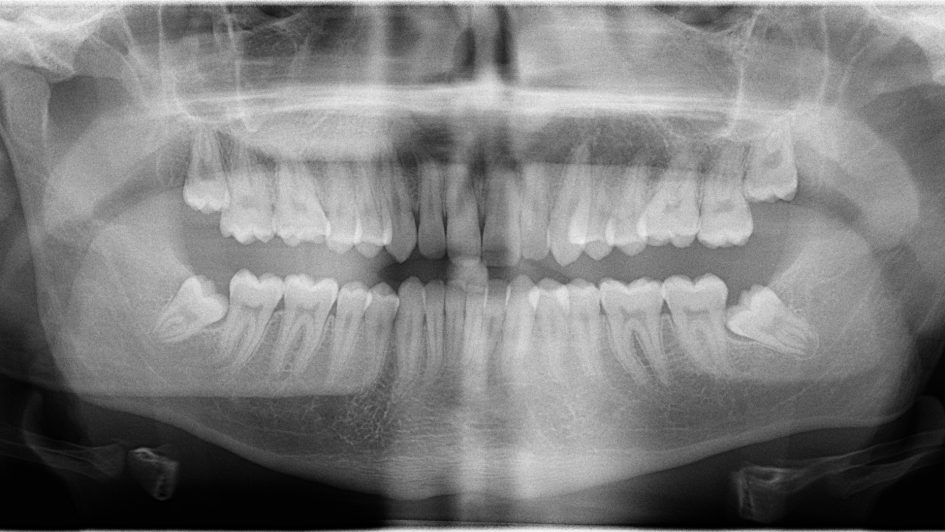

Para conocer hacia donde está orientado el diente, es necesaria la realización de radiografías intraorales y/o extraorales (ortopantomografía, TAC, CBCT).

Los dientes que se quedan incluidos en el hueso y la encía con más frecuencia son las muelas del juicio y los caninos (colmillos).

En el caso de las muelas del juicio, suele darse porque se encuentran en posición inclinada u horizontal y no pueden llegar a salir en esas circunstancias, o porque no poseen espacio suficiciente en la arcada para posicionarse. En este caso la mayoría de las veces se recomienda la extracción de estas piezas.

Es también muy frecuente encontrarse con caninos incluidos en el hueso y la encía que por su posición, necesitan de una ayuda para salir y ponerse entre el premolar y el incisivo lateral.

Los caninos erupcionan en torno a los 13 años de edad. En caso de retrasarse, es recomendable ir realizando un seguimiento radiográfico periódico para comprobar si con el tiempo el diente va acercándose a la encía. Si por lo contrario no cambia su posición y además, la pieza está orientada hacia otra posición, el profesional considerará la opción de una fenestración de dientes.